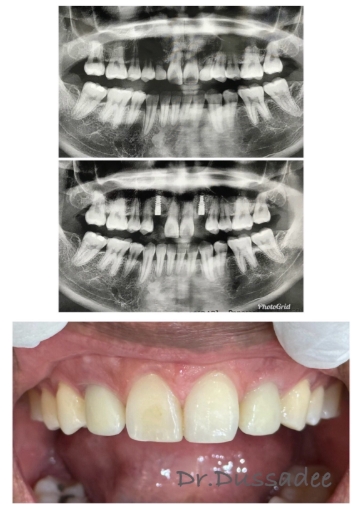

เคสคนไข้รากเทียม 1

เคสคนไข้รากเทียม 2

เคสคนไข้รากเทียมพร้อมฟันปลอม

เคสคนไข้รากเทียม